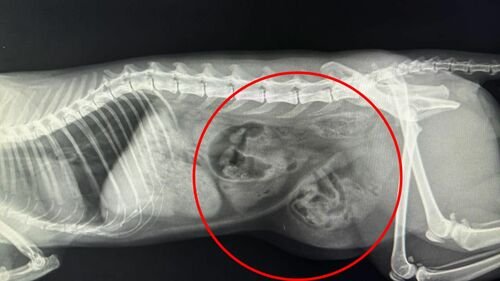

Meu gato Romeu foi atropelado dia 09/04/24 perto das 20h. No mesmo dia passou por uma cirurgia de emergência chamada “Hernioplastia” (A hérnia dele se rompeu deixando o intestino dele solto pelo corpo). Além disso o Romeu fraturou 3 ossos, sendo 2 na perna e 1 na parte de cima dele. Acontece que todos os nossos fundos foram na cirurgia de Hernioplastia, e precisamos de dinheiro para fazer a segunda cirurgia dele para corrigir os ossos quebrados…